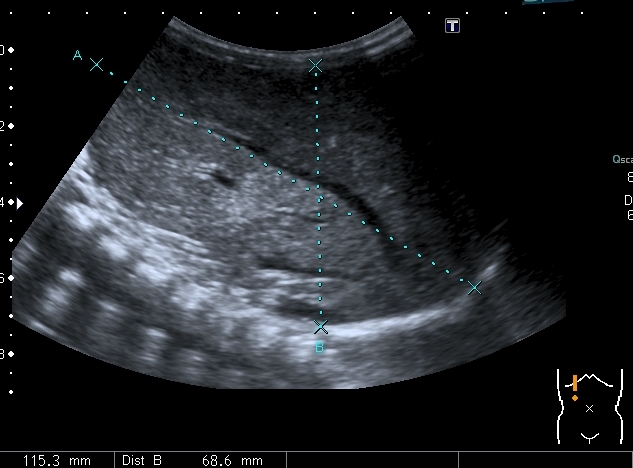

Левая доля

Левая доля прилежит к селезёнке, оттесняет её вниз и дорзально

Паренхима печени -гиперэхогенная , неоднородная, практически полностью замещена нодулярными образованиями, некоторые из них с "гало" и кальцификацией